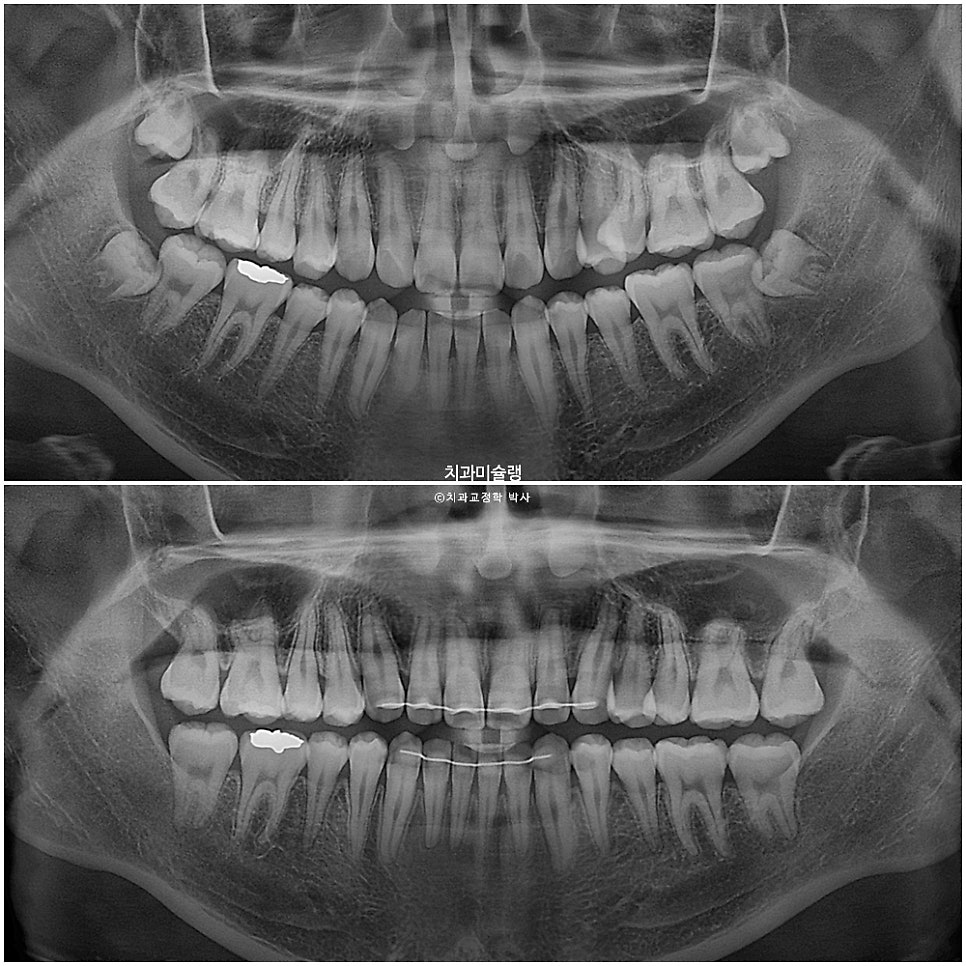

치근평행도는 양호하고

2년에 가까운 치료기간동안 안모 변화를 이러합니다.

턱뼈가 어긋난 상태에서 교정만으로 앞니 교합을 맞추면 위 앞니는 정상각도보다는 더 커지며 처음보다 좀더 뻗치게 됩니다. 또 아래앞니는 정상보다 더 뒤로 누운 각도가 될수밖에 없습니다.

이부분에 대해 허용한다면, 양악수술이나 발치 없이도 주걱턱 부정교합에서 교정만으로 좋은 결과가 나옵니다.